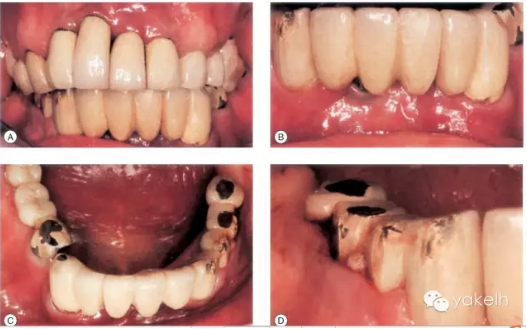

這個(gè)病例使用種植修復(fù),效果較差。在上頜前牙區(qū),存在嚴(yán)重的美學(xué)問題(圖.12A)。

下頜有一顆種植體位于LR1和LR2之間的外展隙區(qū)域,這不僅影響美觀,同時(shí)也不利于口腔衛(wèi)生的維護(hù)(圖.12B)。

大多數(shù)修復(fù)體都發(fā)生了崩瓷,治療效果不佳(圖.12C)。LR5種植體周圍溢膿,存在種植體周圍炎(圖.12D)。

圖.12 該病例臨床效果差。多個(gè)修復(fù)體失敗,發(fā)生了種植體周圍炎,還存在美學(xué)問題。